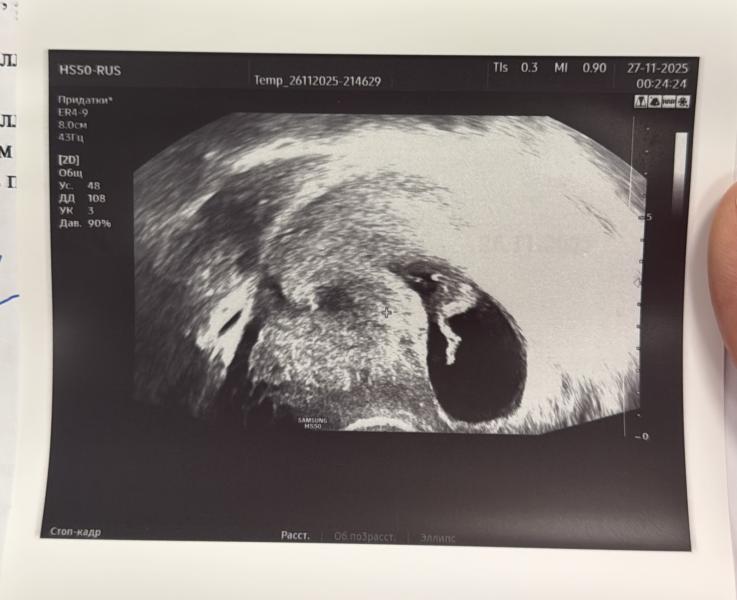

Ножка, 11 недель😌

🤣🤣🤣 Ага, я не могу поверить, что вот эти 42 мм во весь рост через какое-то время будут иметь не просто ногу больше моей, а еще и свое мнение🤣